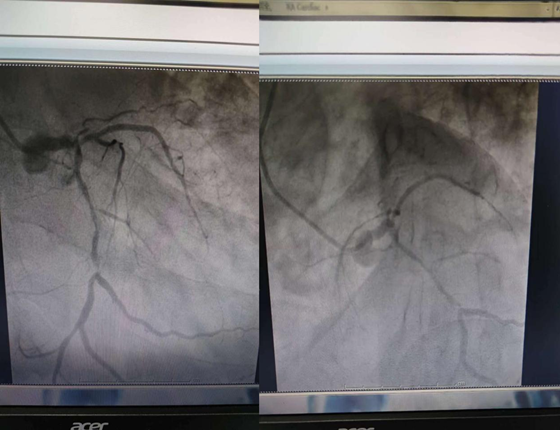

住院后完善冠脉造影检查结合患者病情及冠脉造影结果,诊断为缺血性心肌病,冠状动脉多支多处严重狭窄病变,属于慢性完全闭塞性病变(简称CTO),且合并有钙化病变,这类患者发生严重心血管事件的相对危险度更高,堪称冠状动脉最可怕的“魔头”之一。对于如此严重的CTO病变,直接植入支架难以通过病变区域,且极有可能出现血管“撕裂伤”,导致冠脉夹层、穿孔等严重并发症,手术所需时间长,必要时需要行冠脉旋磨术。告知患者及家属手术方式及相关风险后,患者及家属经过慎重考虑强烈要求行PCI术。

术前造影